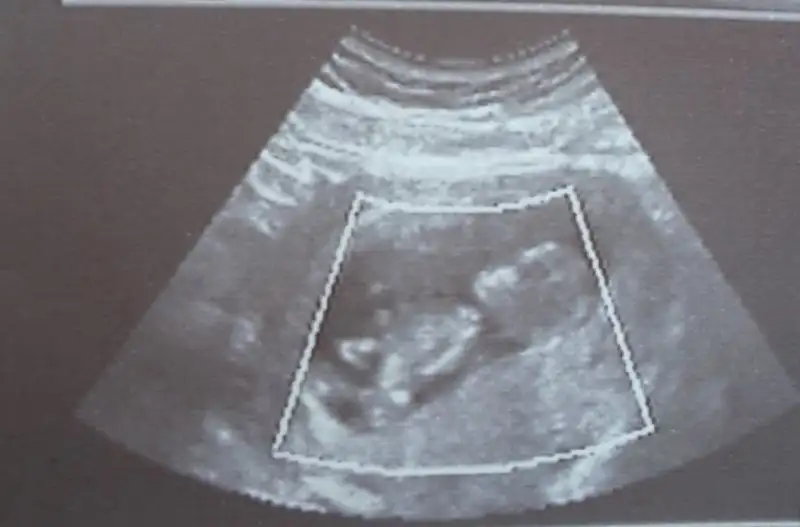

Bunlarda benim minik bebişim 3 boyutluda baktı cok güzeldi hiç durmadı sürekli eller kollar hareketliydi :) bebeğimin durumu cok iyiymiş 2li test için kan verdik çarşamba gününe cıkacakmış. ama doktorum memur olmuş baska bi yere atanmış gidiomuş :( yeni doktor bulmam gerekio nası bulcam nası karar verecem bilmiorum :( cinsiyetini göremedi bacaklarını kapatıyor dedi çarsamba testleri göstermeye gittiğimde yeniden bakmasını isticem bakalım gösterecekmi:) raporisticektim ama kötü haberi alınca bişi diyemedim :(:(